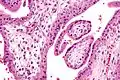

Micrografía que muestra vellosidades coriónicas. Aumento intermedio. Tinción H&E.